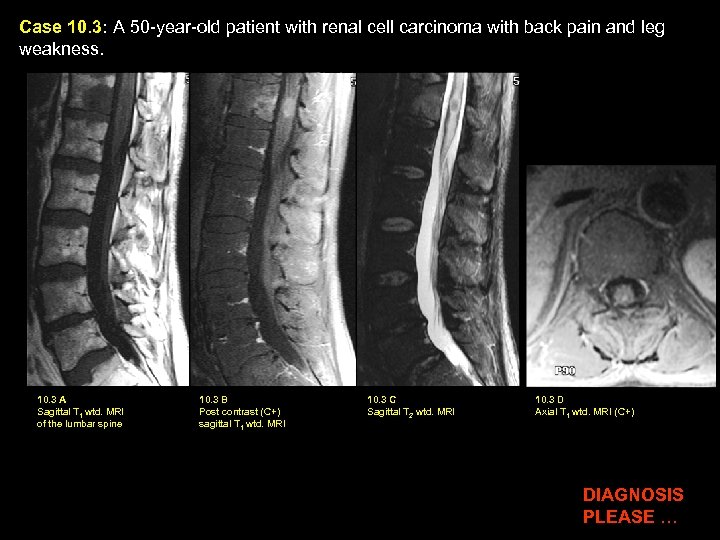

Case 10. 3: A 50 -year-old patient with renal cell carcinoma with back pain and leg weakness. 10. 3 A Sagittal T 1 wtd. MRI of the lumbar spine 10. 3 B Post contrast (C+) sagittal T 1 wtd. MRI 10. 3 C Sagittal T 2 wtd. MRI 10. 3 D Axial T 1 wtd. MRI (C+) DIAGNOSIS PLEASE …

Case 10. 3: A 50 -year-old patient with renal cell carcinoma with back pain and leg weakness. 10. 3 A Sagittal T 1 wtd. MRI of the lumbar spine 10. 3 B Post contrast (C+) sagittal T 1 wtd. MRI 10. 3 C Sagittal T 2 wtd. MRI 10. 3 D Axial T 1 wtd. MRI (C+) Findings: : Bony metastasis (yellow arrow in A, B, C) is seen involving the T 12 vertebral body. Intramedullary location of metastasis within the distal thoracic cord, is verified on post contrast sagittal image (red arrow in B) and axial image (red arrow in D). Edema (green arrow in C) within the thoracic cord is best shown on T 2 wtd. image C. Diagnosis: Bony Metastasis and metastasis to the Spinal Cord

Metastasis to the Spinal Cord Incidence: Rare Primary Sites: Intracerebral Tumors: • Lung • Medulloblastoma • Breast • Ependymoma • Melanoma • Glioblastoma • Kidney • Germ Cell Tumor • Lymphoma/Leukemia Route of Spread: Arterial seeding, Batson’s venous plexus, Drop metastasis (from intracerebral tumor)